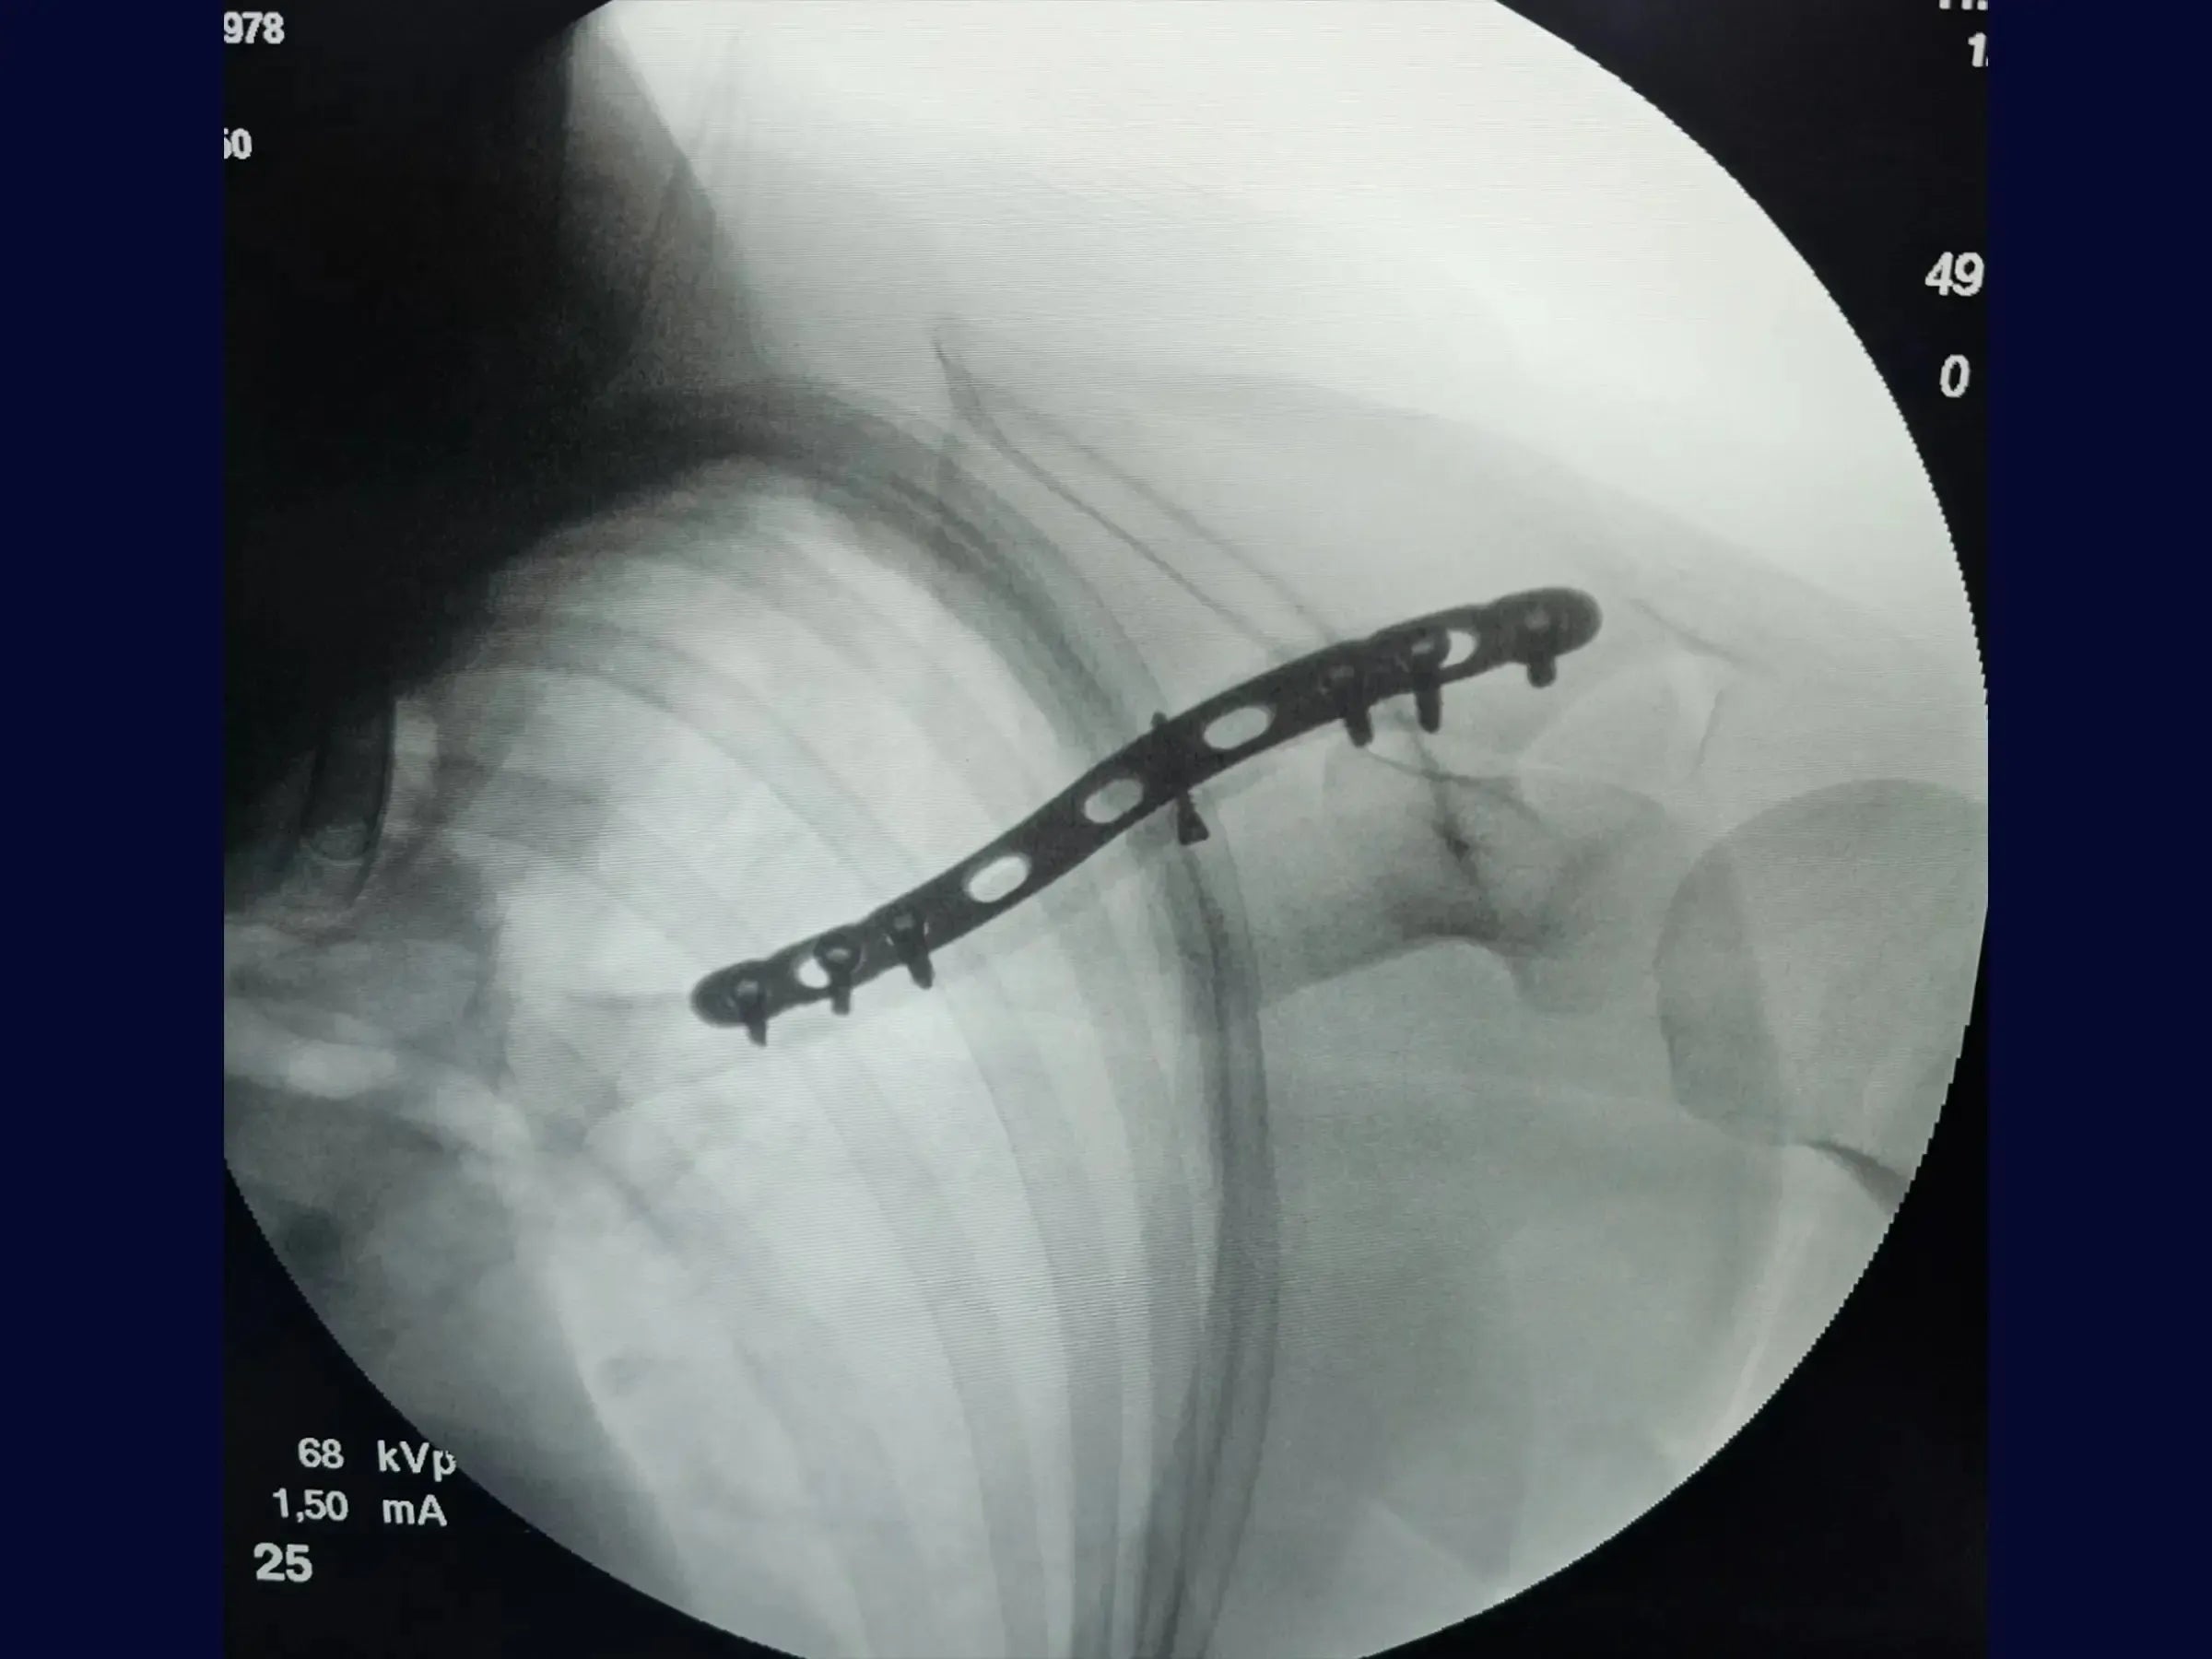

- Acessos Cirúrgicos Otimizados: Confecção e utilização de dois portais (lateral e medial) para um trajeto seguro da placa em ponte.

- Planejamento de Implante e Túnel Subcutâneo: Procedimentos para mensuração da placa e criação de túnel subcutâneo entre os portais para inserção minimamente invasiva.

- Fixação Biomecanicamente Eficaz: Estratégias para inserção de parafuso interfragmentar em traços oblíquos e sequência de fixação com parafusos nos terços lateral e proximal da clavícula.

- Fechamento por Planos Otimizado: Técnicas de sutura profunda, ligando o músculo peitoral ao trapézio, e sutura intradérmica para resultado estético e funcional superior.